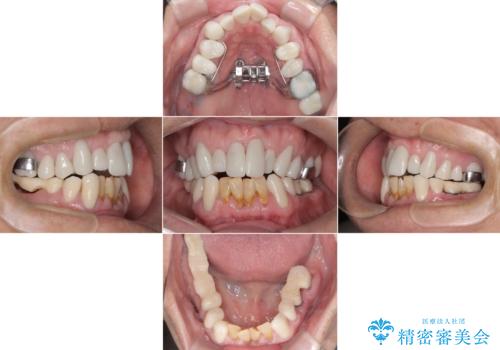

- 強い酸によって歯が広範囲にわたって侵食され、「歯がボロボロになった」と主訴に来院されました。詳細な診査の結果、重度の酸蝕症と診断。失われた歯質や咬み合わせの崩壊が著しいことから、単一の治療では対応が困難と判断し、矯正治療、インプラント治療、セラミック治療を組み合わせた総合的な治療計画を立案しました。矯正治療後に最終的にセラミックを用いて機能性と審美性を回復。患者様と綿密な話し合いを重ね、長期的な口腔内の健康維持を見据えた最適な治療を行いました。

酸蝕症の原因に関しては、医科のほうで解決済みでしたので、失われた機能、審美性の回復のため矯正治療によって歯並びと咬み合わせのバランスを整えセラミックによる修復を行ました。

保存できないと判断した歯は抜歯しインプラントにて治療をおこなっています。

矯正後、歯肉の形態不良のため、歯周外科を行い連続性を獲得しています。